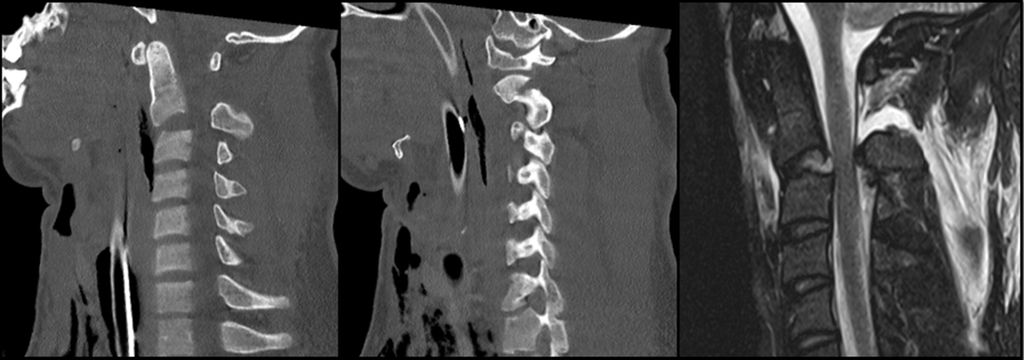

Atlasfrakturen entstehen durch axial einwirkende Kraft auf den Atlasbogen und machen 2 bis 13% aller zervikalen Verletzungen sowie 1 bis 3% aller Wirbelsäulenfrakturen aus. Besonders bei geriatrischen Patient:innen treten sie häufig in Kombination mit Odontoidfrakturen auf. Die mögliche begleitende traumatische Ruptur des Ligamentum transversum atlantis (TAL) ist von entscheidender Bedeutung, da die Stabilität bei isolierten Atlasfrakturen maßgeblich von der Integrität dieses Bandes abhängt. Der Verdacht auf eine Ruptur kann in der konventionellen transoralen Densaufnahme suszipiert werden, wenn die Massae laterales eine Verschiebung gegenüber der Axis aufweisen. Eine Verschiebung um mehr als 7mm in den koronalen CT-Aufnahmen gilt als Hinweis auf eine Ruptur des TAL. Dieses Kriterium wird auch als Spencer-Regel bezeichnet.7,8 Mit der MRT kann die Verletzung des Ligamentums nachgewiesen werden. Atlasfrakturen wurden bereits 1919 von Jefferson beschrieben und 1976 von Gehweiler vollständig klassifiziert. Typ I umfasst isolierte Frakturen des vorderen Atlasbogens, die als stabil gelten und meist konservativ mit einer weichen Schanzkrawatte behandelt werden können. Typ II beschreibt Frakturen des hinteren Atlasbogens, die ebenfalls als stabil gelten, sofern keine Dislokation des Frakturfragments vorliegt, und ebenso konservativ behandelt werden können. Frakturen, die sowohl den vorderen als auch den hinteren Atlasbogen betreffen, werden als Typ III oder Jefferson-Fraktur bezeichnet. Diese werden weiter in Gehweiler IIIa mit intaktem Ligamentum transversum atlantis und als stabil eingestuft sowie in Gehweiler IIIb mit rupturiertem TAL und als instabil klassifiziert. Bei Letzterem ist die dorsale Stabilisierung von C1/C2, beispielsweise transartikulär nach Magerl oder mittels Verschraubung nach Harms, die Therapiemethode der Wahl. Verletzungen des TAL können mittels der Dickman-Klassifikation weiter unterteilt werden, wofür eine MRT-Untersuchung erforderlich ist. Typ IV umfasst isolierte Frakturen der Massa lateralis, bei denen eine Operation nur selten notwendig ist, außer bei Gelenksflächenzertrümmerung. Typ V beschreibt Frakturen des Processus transversus atlantis, die zwar als stabil gelten, bei denen jedoch stets eine Verletzung der Arteria vertebralis ausgeschlossen werden muss. Schwere Komplikationen sind bei Atlasfrakturen selten, neurologische Ausfälle treten nur gelegentlich auf. Die externe Immobilisierung isolierter Atlasfrakturen führt in der Regel zu guten radiologischen Ergebnissen. Pseudoarthrosen oder Instabilitäten treten selten auf, dennoch berichten viele Patient:innen weiterhin über anhaltende Nackenschmerzen.9